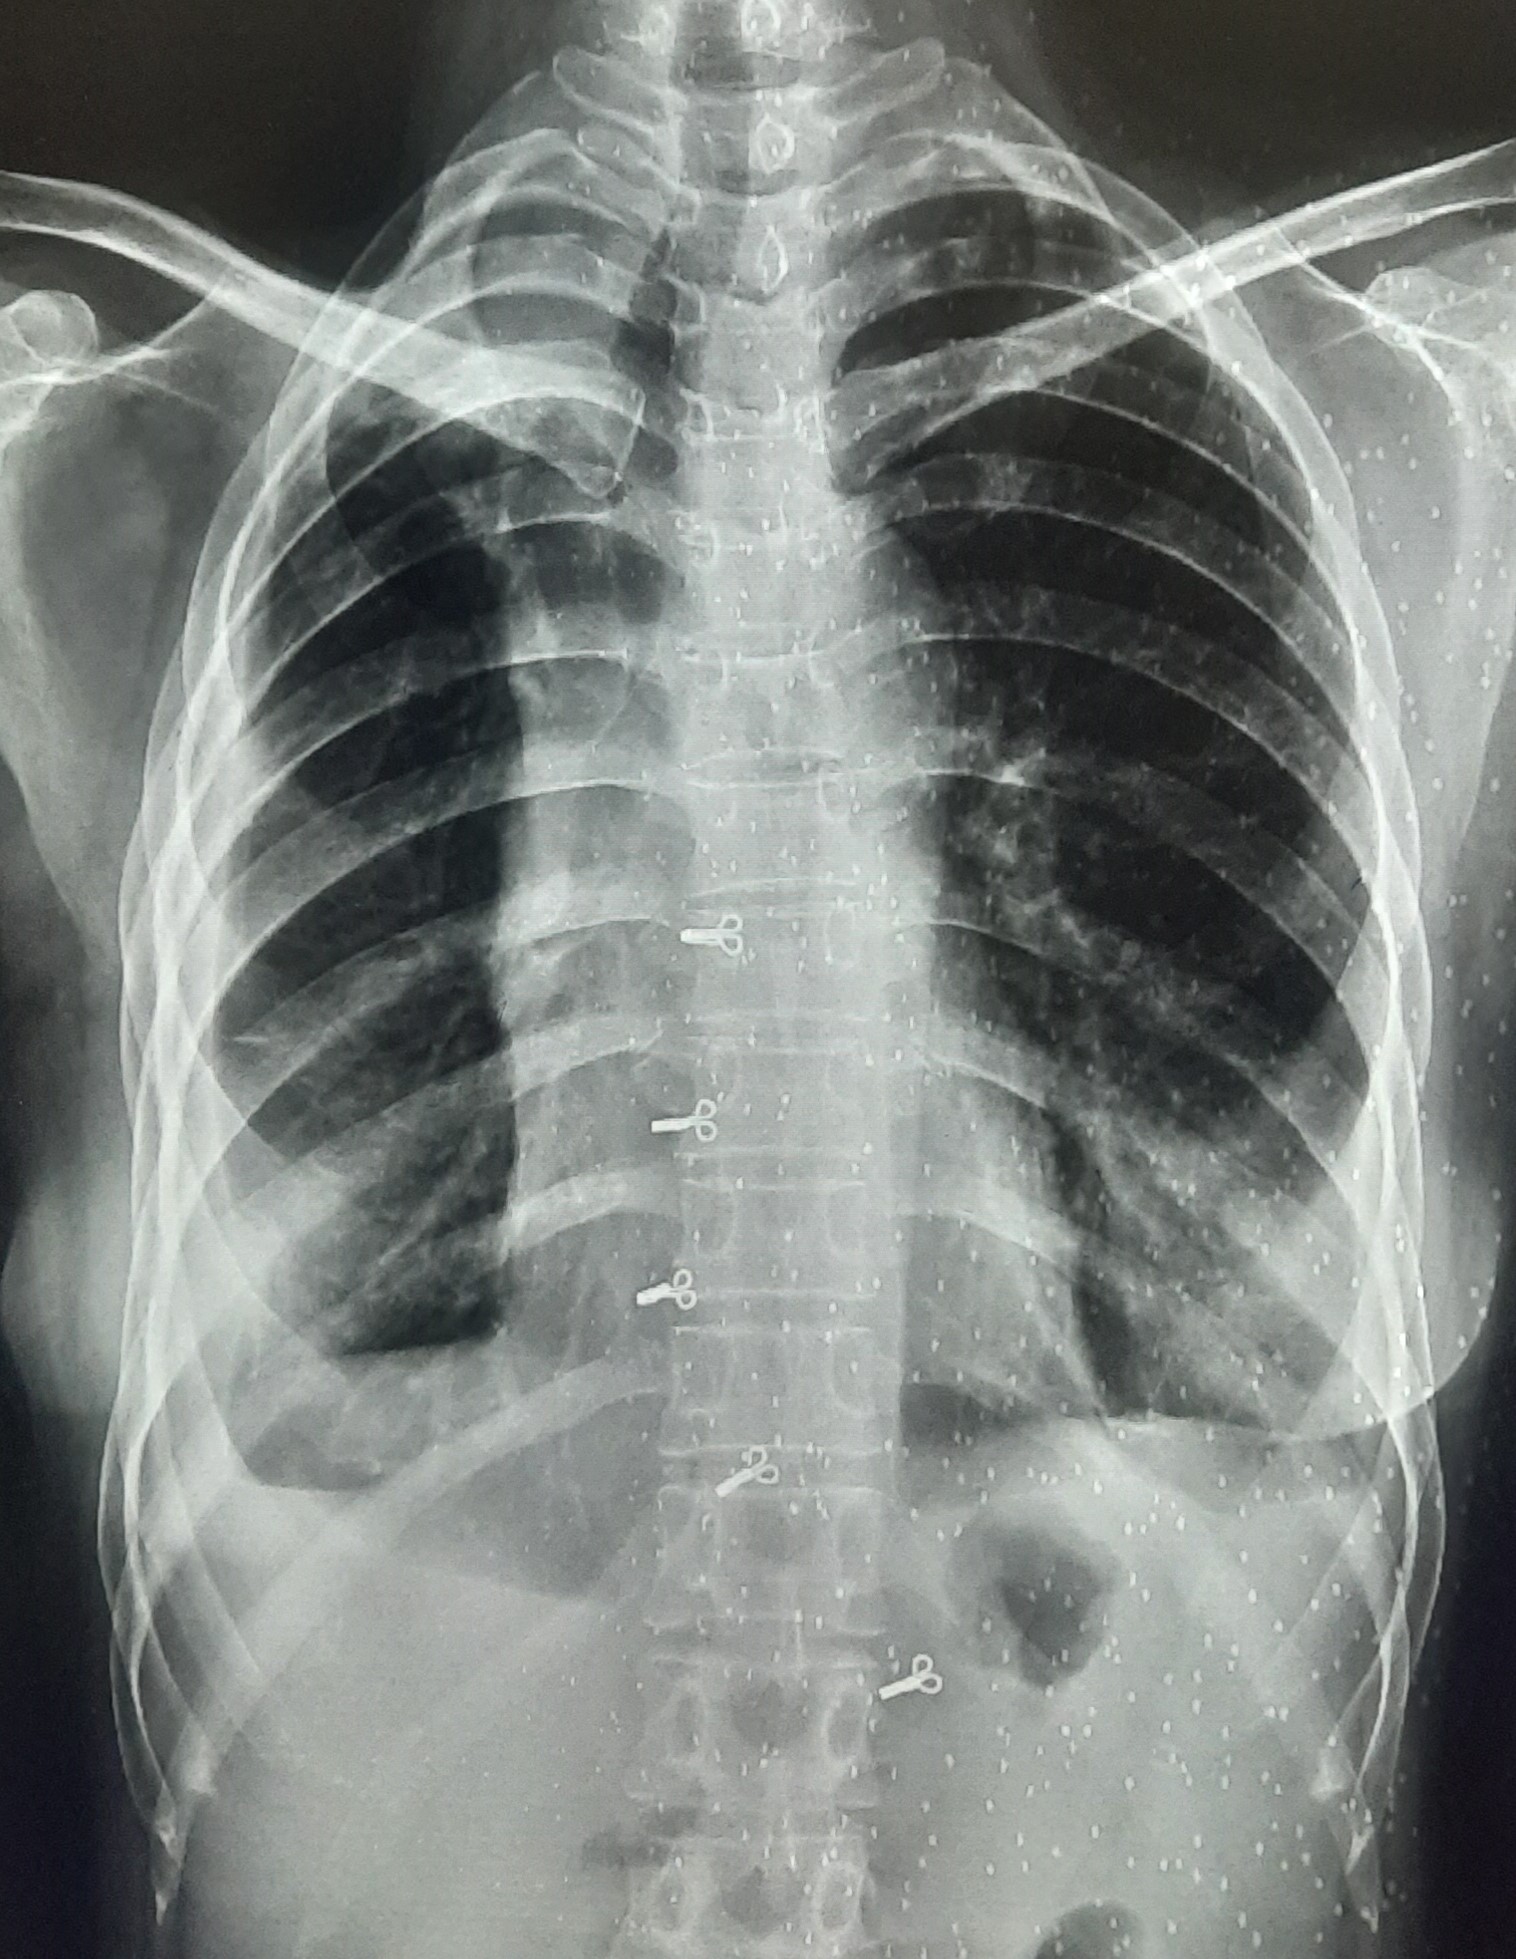

| IGGMC, Nagpur | 29-4189 | IGGMC, Nagpur | Monali Pralhad Milmile | K/C/O Microbiologically Confirmed PTB With Bilateral Pleural Effusion On ATT Since 13-Sep-2024 |

| Chest X-Ray Image |